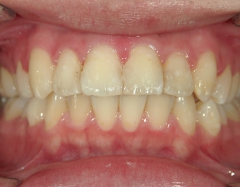

矯正歯科 治療後矯正歯科 プチワイヤー矯正 治療後矯正歯科(プチワイヤー矯正)治療後

矯正歯科 治療後

no.6_8296_治療後_右.jpgno.6_8296_治療後_正面.jpgno.6_8296_治療後_左.jpg